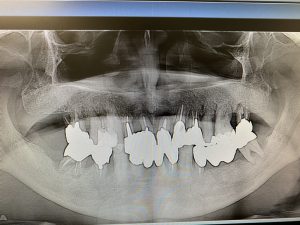

(Before )

抜歯即時埋入(抜歯と同時にインプラント埋入手術を行う)さらに、同日に直ぐに噛めるように暫間的なインプラントまでも入れる手技、、

抜歯と同時にインプラントを埋入する手技は患者さんにとっては『オペ』が一度で済む利点がありますが術者の高いスキルが要求されるオペです。今回はさらに患者さんの食と生活の質(Q.O.L)を落とさず日常生活を過ごして頂く為に補助的インプラントを同時に埋入し『噛めないなら→噛める』場所を仮にでも作ろう!(CT解析後にガイドプレートなどに頼るオペは時にブレがあり現場で使えない事しばしば)(理事長のオペはそれらを踏まえて先の先を見越し事前の解剖学的組織や形態を頭と腕に叩き込みフリーハンドで施術します)